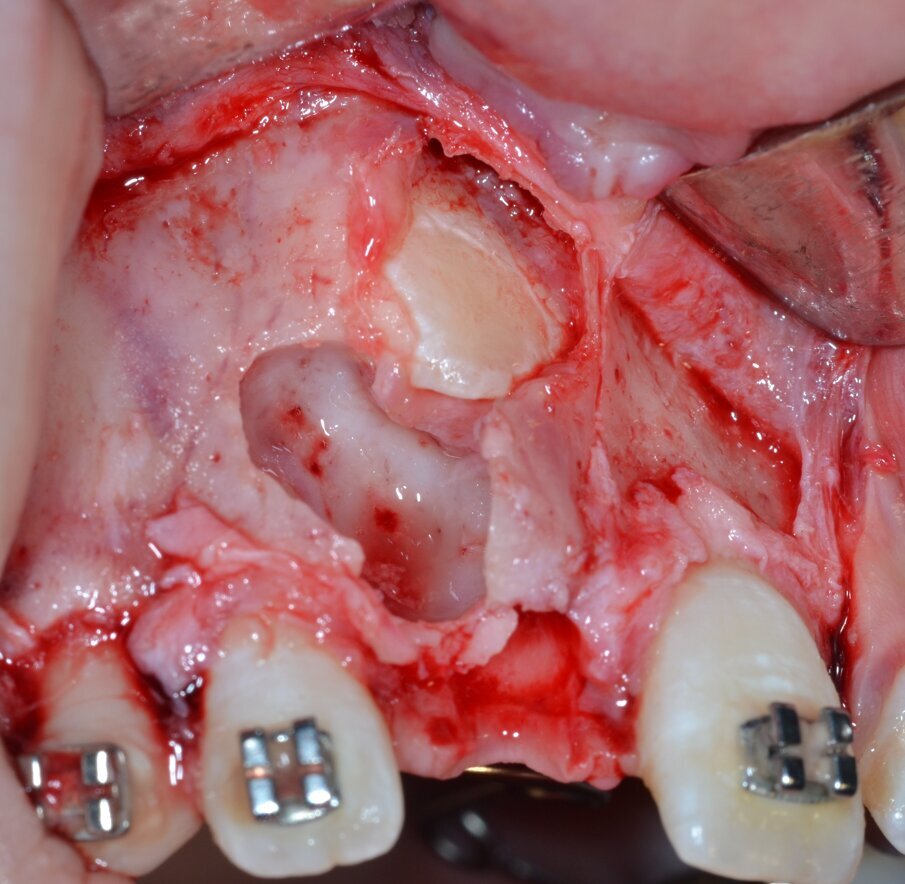

Si procede al clivaggio e all’enucleazione in toto della massa neoformata mediante una leva dritta (Fig. 9) seguita da un’accurata revisione chirurgica della cripta ossea residua (Fig. 10). Il pezzo operatorio viene inviato per l’esame istologico, che confermerà in via definitiva la diagnosi di odontoma composto (Figg. 11, 12). Poiché il piano di trattamento prevede di eseguire l’ancoraggio ortodontico dell’elemento ritenuto nella stessa seduta operatoria, la corona dentaria dell’elemento 1.1 viene esposta chirurgicamente per mezzo di un inserto piezoelettrico dedicato montato su un manipolo ad ultrasuoni (ES010T Esacrom Srl, Imola, Italia) (Fig. 13).

Fig. 10_Revisione chirurgica della cripta ossea residua.

Fig. 13_Esposizione chirurgica della corona dentaria di 1.1.